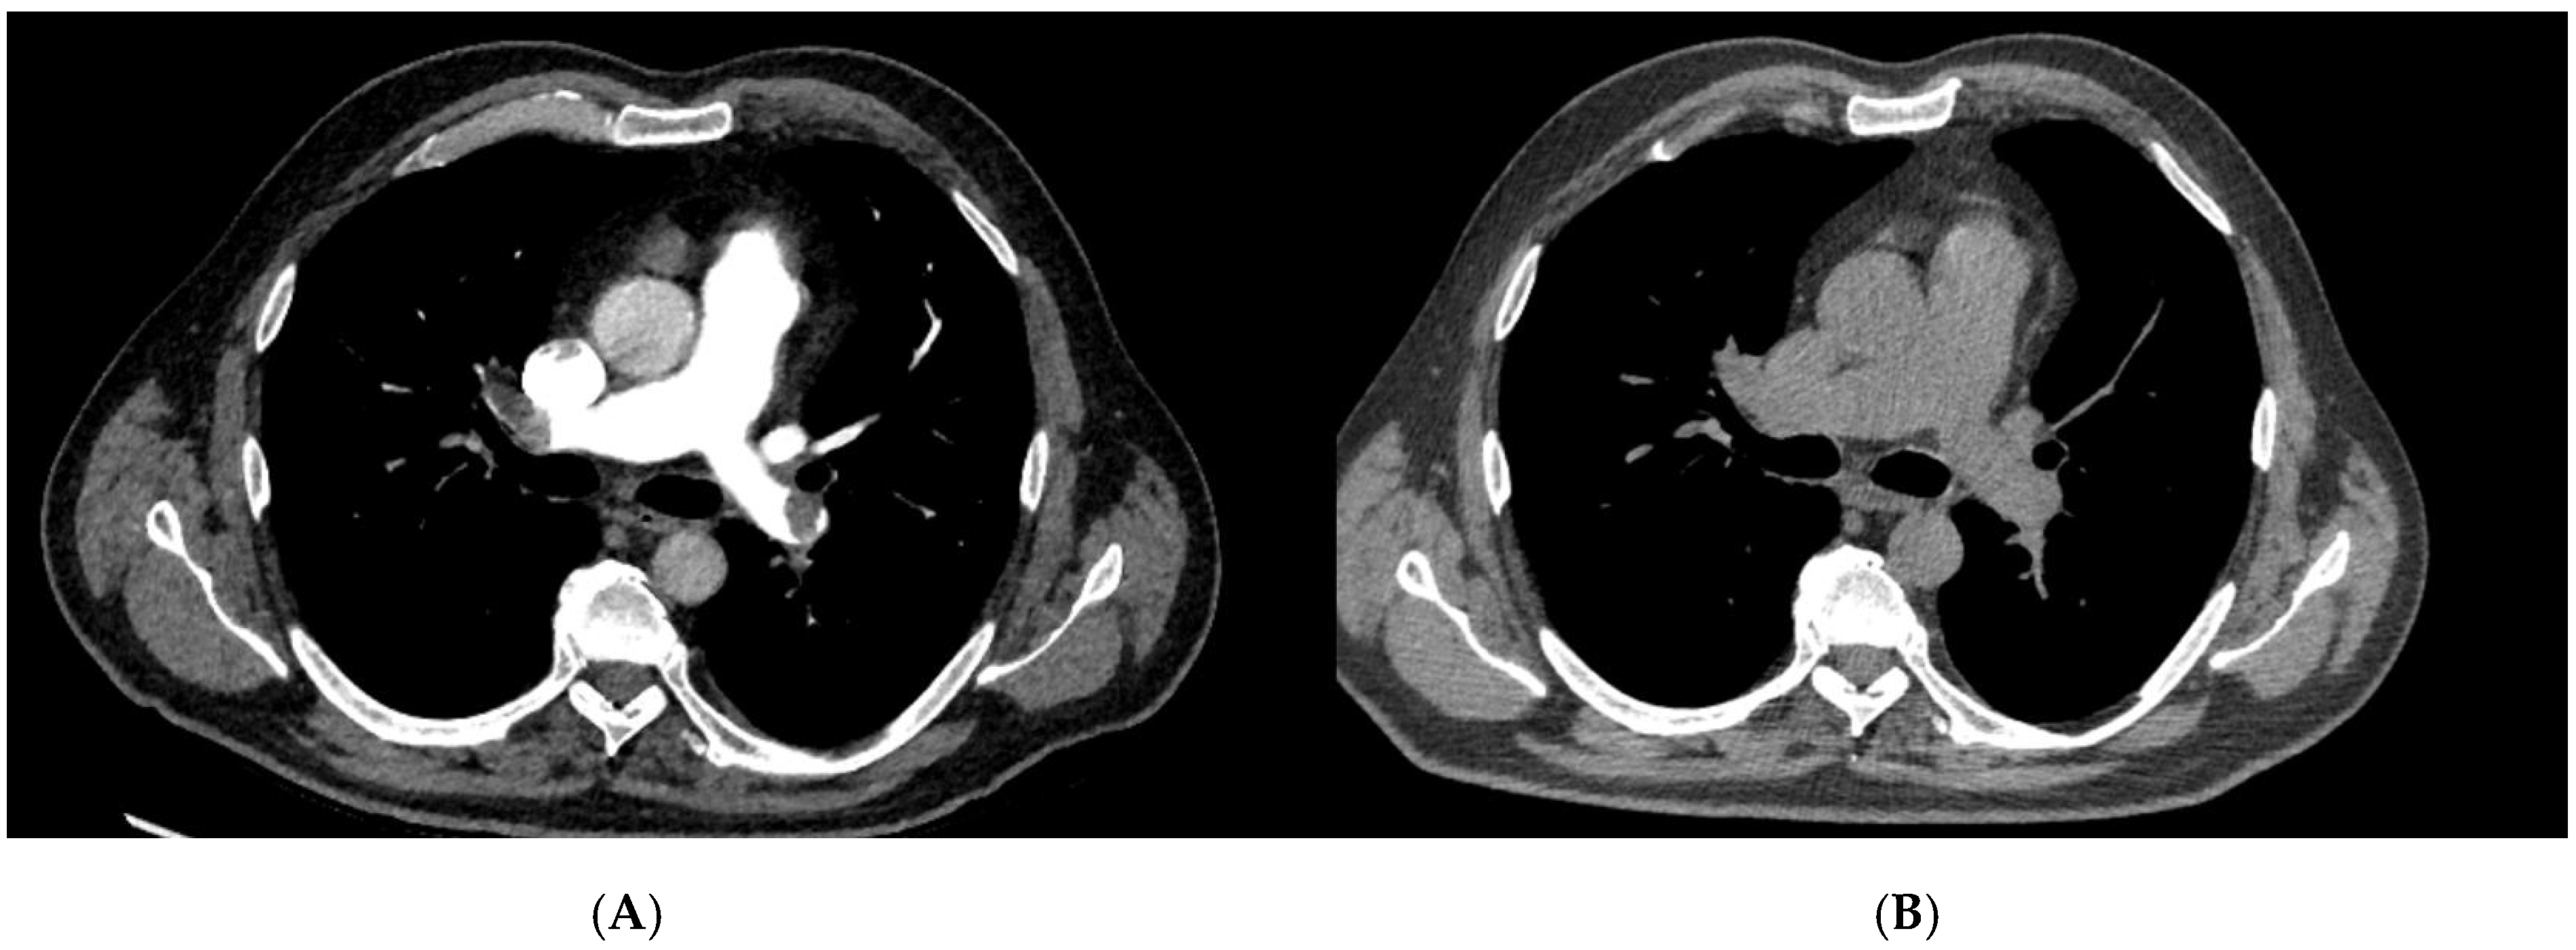

| CTPA | Computed Tomography Pulmonary Angiography |

| Localization of PE via CTPA | ||||

| Bilateral central | 79 | 40 | 39 | 0.790 |

| Bilateral segmental | 1 | 1 | 0 | 0.999 |

| Right sided central | 3 | 2 | 1 | 0.5595 |

| Left sided central | 1 | 0 | 1 | 0.999 |

| Left sided segmental | 1 | 0 | 1 | 0.999 |

| Peripheral | 1 | 1 | 0 | 0.999 |

| not specified | 10 | 4 | 6 | 0.506 |